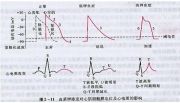

| 2021年7月26日 (一) 20:03 | 血钾浓度异常EKG.jpg (文件) |  |

51 KB | Uploaded with SimpleBatchUpload | 3 |